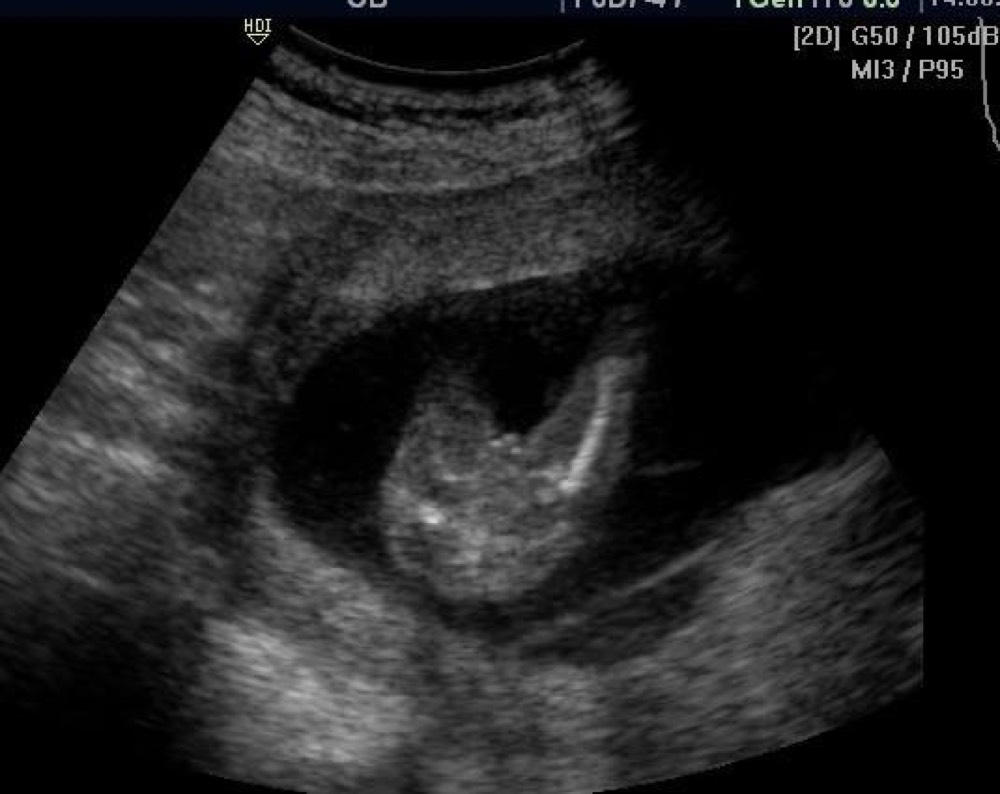

12 Les signes qui doivent attirer votre attention;Toute bourse aiguë exige une évaluation urgente, dans l'hypothèse d'une torsion menaçant une gonade Elle est avant tout clinique, mais peut comporter une utilisation sélective d'examens complémentaires, dont souvent l'échographie, à confier à un opérateur entraîné (1) Torsion du pédicule spermatique (TPS) La douleur3 Comment prendre soin de la peau de votre bébé métis ?

Le bébé nage dans 500 ml de liquide amniotique Chez les petites filles, 6 millions de cellules sexuelles primitives (qui donneront ensuite 1 million d'ovules) sont déjà présentes au niveau des ovaires Le vagin commence à se creuser Chez les petits garçons, les bourses sont encore vides les testicules ne sont pas encore descenduesSupport de Cours (Version PDF) Item 223 Angiomes cutanés Collège National des Enseignants de Dermatologie Date de création du document 1011Debout et la possibilité de chasser le liquide en pressant la bourse Figure 3 Hydrocèle 43 Examens complémentaires L'échographie est l'examen de référence en cas de doute diagnostique Elle met en évidence une lame d'épanchement dans la vaginale et extratesticulaire

Atlas Echographique D Une Bourse Aigue Chez L Enfant L Essentiel Pour S En Sortir Pdf Free Download

La Bourse Aigue De L Enfant Correlations Radiocliniques Urofrance